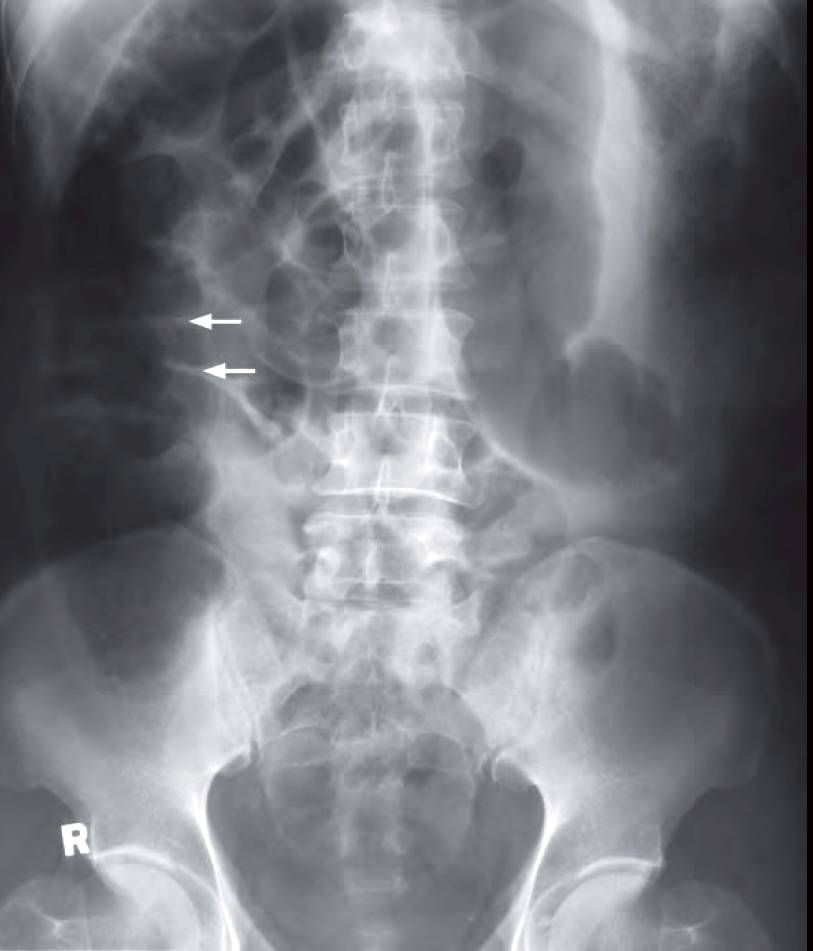

An 80-year-old man presented with colicky abdominal pain, constipation for three days, and repeated vomiting for 1 day. Physical examination showed a distended abdomen with hyperactive bowel sounds. No abdominal mass or organomegaly was detected. Laboratory investigations were unremarkable.

What radiological abnormalities can you see and what’s the diagnosis ?